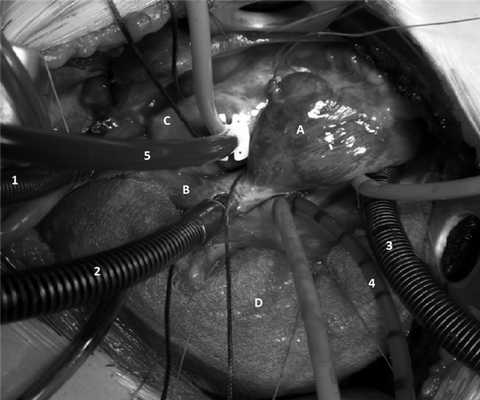

5) аппарат ИК подключается по схеме аорта - бикавальная канюляция (см. рисунок, в); Рисунок 1. Этапы операции при выполнении переднебоковой правосторонней торакотомии. в - установка канюль (А - правое предсердие, В - верхняя полая вена, С - аорта, D - правое легкое, 1 - аортальная канюля, 2 - канюля в верхней полой вене, 3 - канюля в нижней полой вене, 4 - дренаж левого предсердия, 5 - кардиоплегическая канюля).